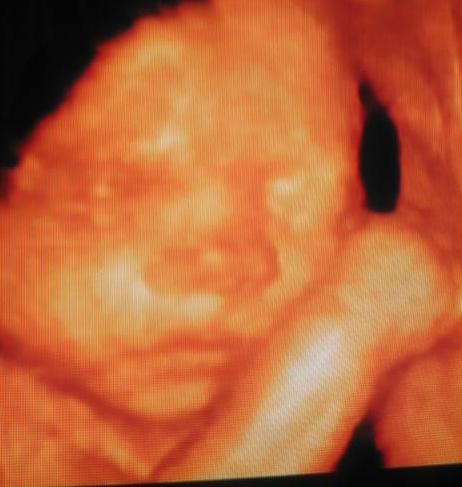

augusztus 1-én megyünk 4D-s uh-ra, már nagyon várom, aztán 6-án majd a 28 hetes uh-ra. Ja és július 26-án megyek a védőnőhöz.

Egyébként pont úgy nézett ki,mint ahogy a 4D-s fényképen! :lol:

A tavalyi bébink is pont úgy nézett ki, mint a 4D-s felvételen.

Megpróbálom feltölteni neked!